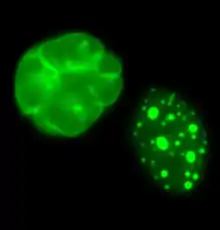

Use in progeria

Studies have been published indicating that farnesyltransferase inhibitors such as lonafarnib a synthetic tricyclic derivative of carboxamide with antineoplastic properties can reverse instability of nuclear structure due to the genetic mutation of the LMNA gene. The drug has been used to treat children suffering from Hutchinson–Gilford progeria syndrome.[6] Results of the first-ever clinical drug trial for children with progeria, demonstrated the efficacy of a farnesyltransferase inhibitor (FTI). [7]